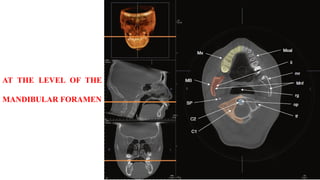

AT THE LEVEL OF THE

MANDIBULAR FORAMEN

AT THE LEVELOF THE MANDIBULAR FORAMEN